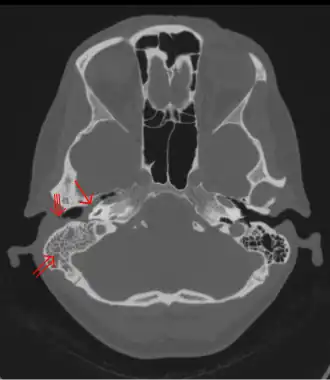

Typisch für die Mastoiditis ist die neuerliche Zunahme der Ohrenschmerzen bei einer akuten Mittelohrentzündung nach anfänglicher Besserung oder die unveränderte Fortdauer der Beschwerden über die dritte Krankheitswoche hinaus. Der eitrige Ausfluss aus dem Gehörgang bleibt bestehen oder tritt wieder auf und das Trommelfell zeigt unverändert eine Verdickung und Rötung. Die Druckempfindlichkeit hinter dem Ohr und eine Senkung der hinteren oberen Gehörgangswand machen die Diagnose sicher, eine Schwellung hinter dem Ohr mit Abstehen der Ohrmuschel lassen keinen Zweifel mehr zu. Eine Röntgenaufnahme und insbesondere die Computertomographie zeigen einen knöchernen Destruktionsherd.